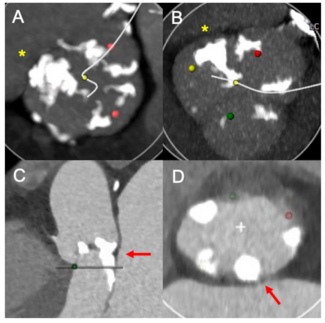

Valeria Duarte, MD; Ponraj Chinnadurai, MBBS; C. Huie Lin, MD, PhD; Maria Katsarou, MD

Endovascular repair of aortic coarctation (CoA) has become an important tool in the treatment of an expanding patient population. In this study, we present our 10-year experience with endovascular repair of CoA.